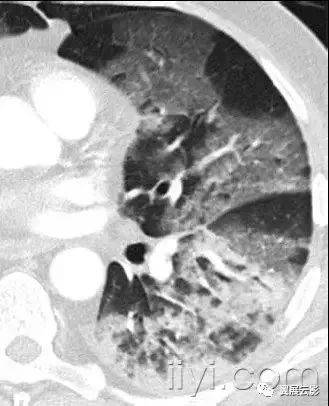

十九、肺实变:

病理学:肺实变是指渗出,或者其他疾病成分替代肺泡内气体,导致肺实变。

平片和CT:肺实变表现为肺实质密度的均匀一致性增高,导致肺血管和气道壁边缘不清。有时可见含气支气管征。只有在极少数的情况下,肺实变的密度变化有助于鉴别诊断,例如脂性肺炎是密度减低,胺碘酮中毒时密度增高。

图示为多灶性的肺实变。